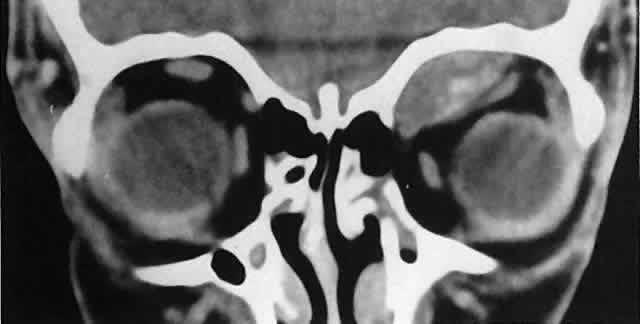

also should be submitted.  Fig. 3. A large metastatic focus of neuroblastoma has destroyed the body of the

sphenoid bone and has extended into both orbital apices. A second site

involves the outer portion of the right sphenoid wing and extends into

the orbit and the middle cranial and temporal fossas. The tumor originated

in the right adrenal gland. Fig. 3. A large metastatic focus of neuroblastoma has destroyed the body of the

sphenoid bone and has extended into both orbital apices. A second site

involves the outer portion of the right sphenoid wing and extends into

the orbit and the middle cranial and temporal fossas. The tumor originated

in the right adrenal gland.